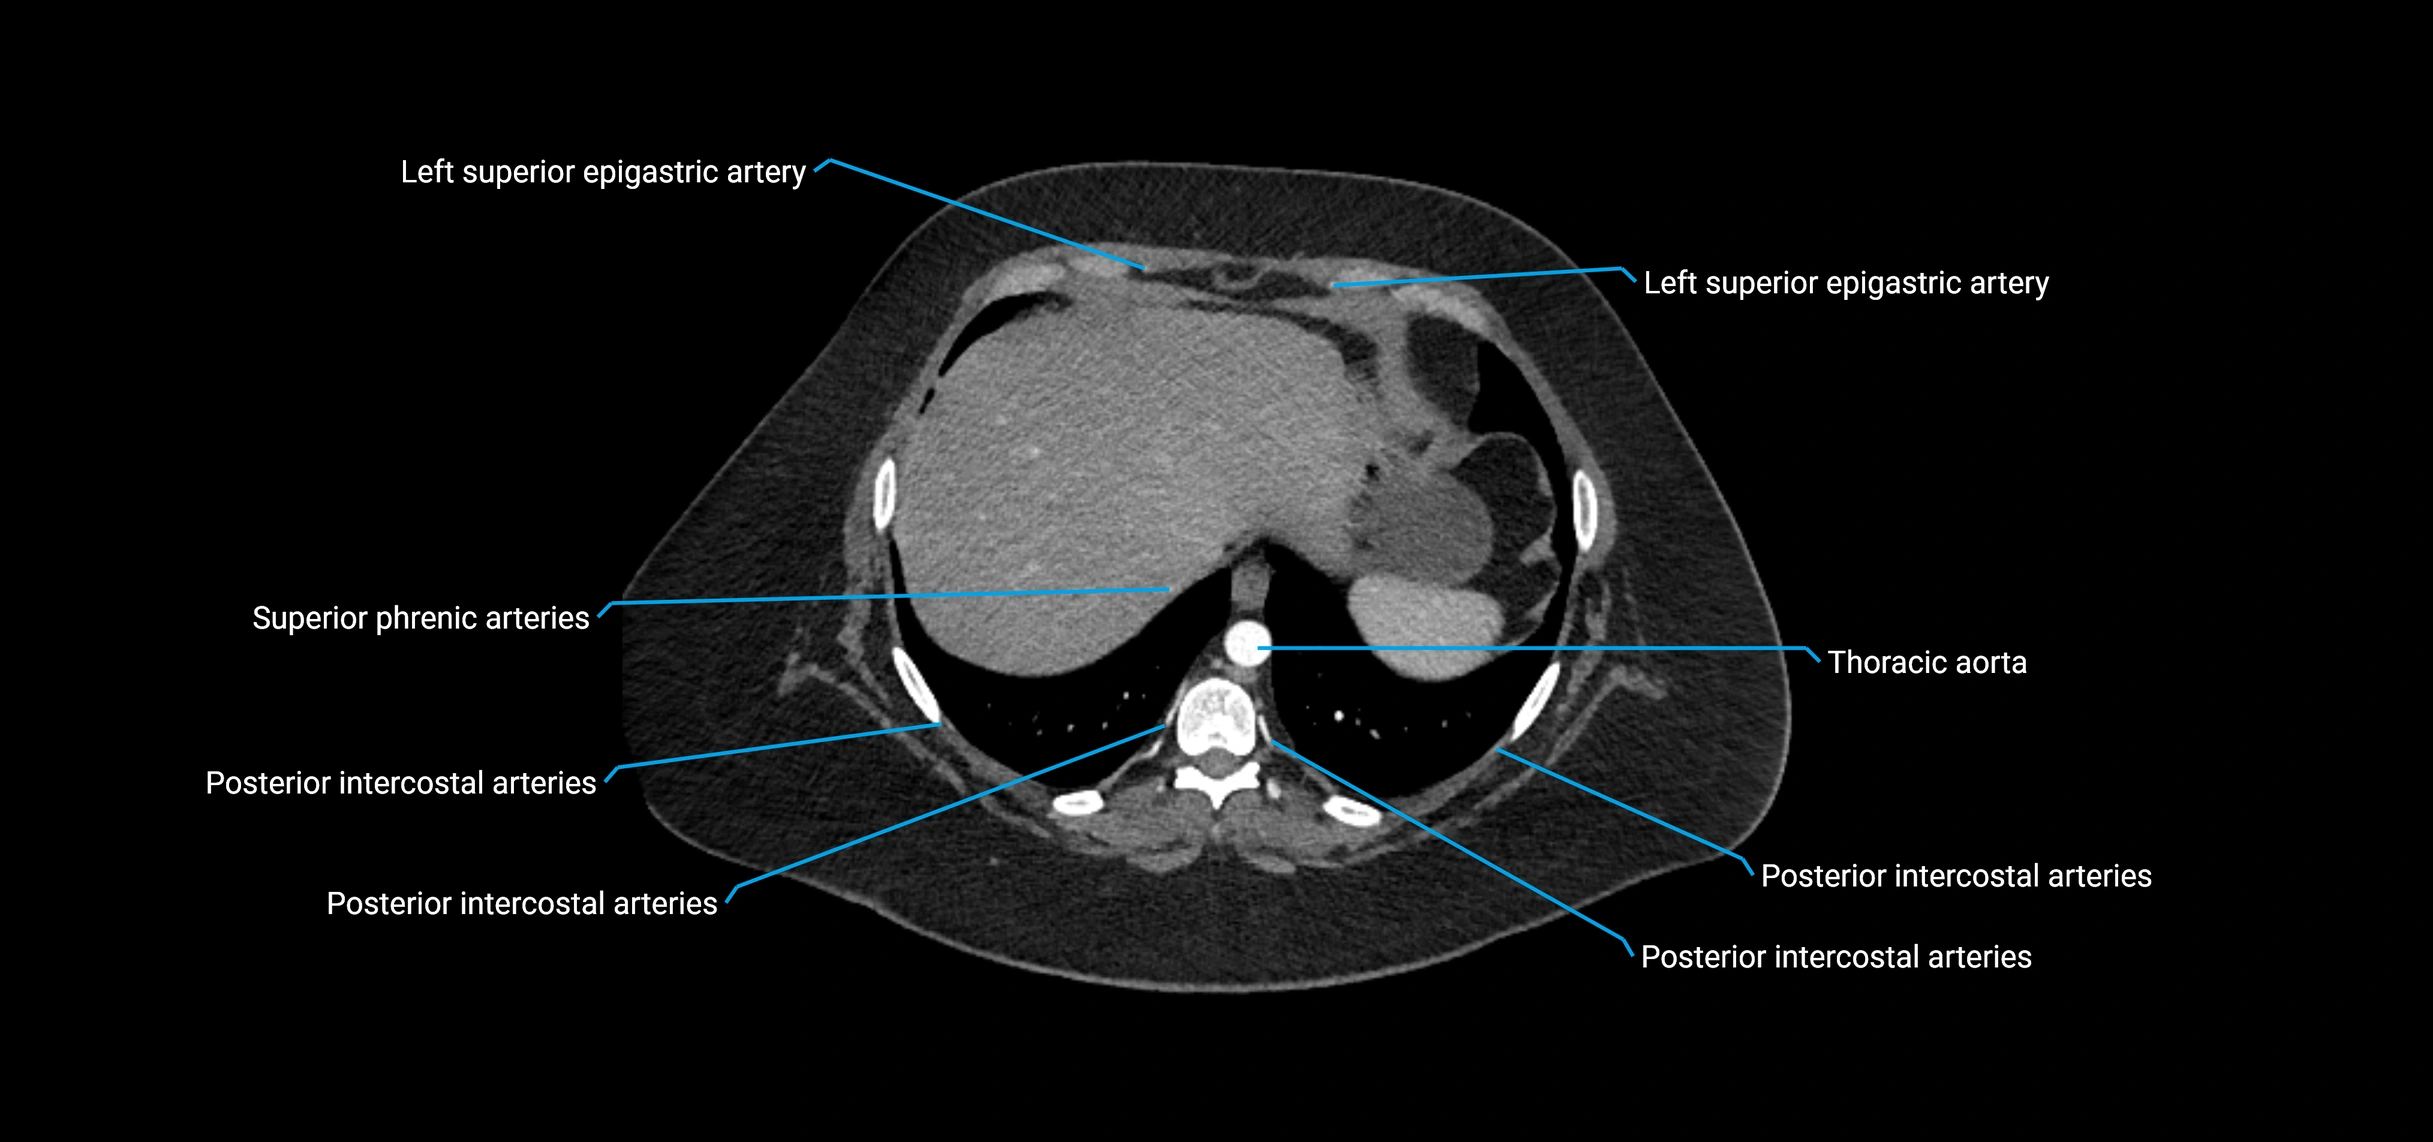

MRI images

image

MRI Appearance

T1-weighted images:

• Flowing blood appears as a signal void (black lumen)

• Vessel wall appears as a thin hypointense rim; retroperitoneal fat enhances contrast

T2-weighted images:

• Lumen remains a signal void due to flow

• Adjacent edema, hematoma, or aneurysm wall thrombus may appear hyperintense

T1 Post-Contrast (Gadolinium-enhanced):

• Aortic lumen enhances brightly and homogeneously

• Clearly demonstrates aneurysm, stenosis, dissection, mural thrombus, or aortic wall enhancement in vasculitis

MRA (Magnetic Resonance Angiography):

• Contrast-enhanced MRA provides high-resolution imaging of the aorta and its branches

• Allows 3D reconstruction of visceral, parietal, and terminal branches

• Excellent for evaluating aneurysm size, dissection flap, stenosis, or preoperative planning

• Non-invasive alternative to conventional angiography